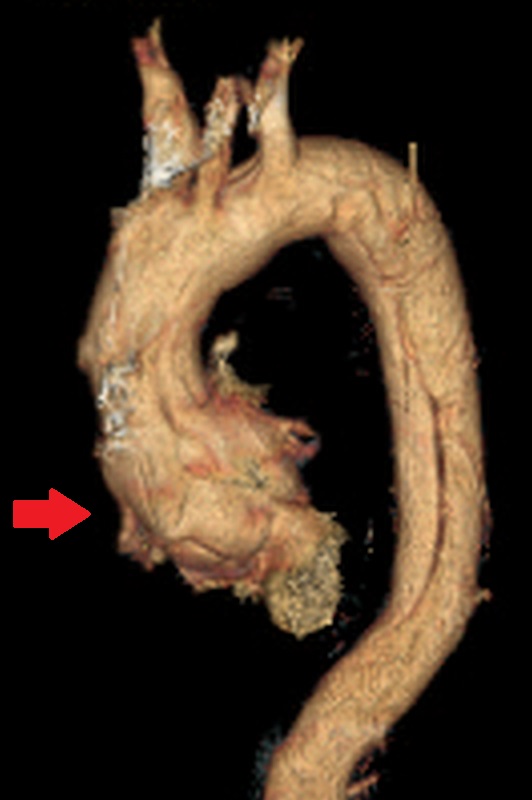

▲術前。